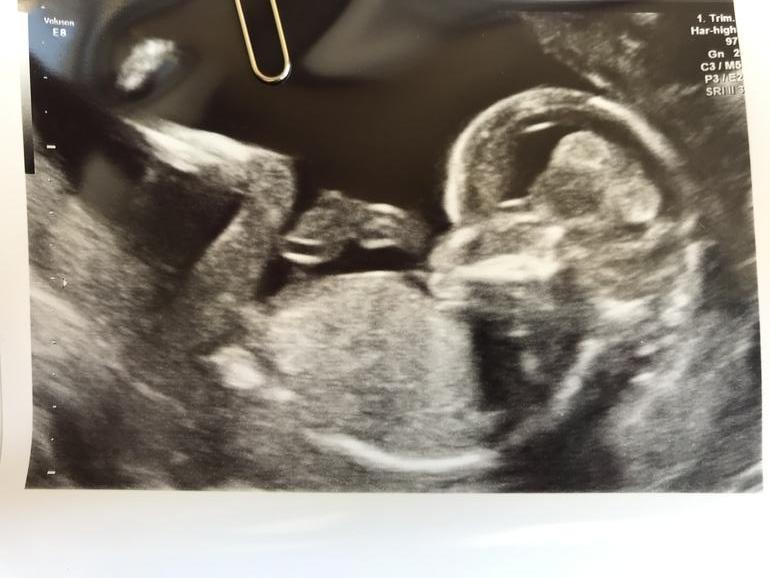

Бугорок мутный и позвоночник до конца не виден, но я за девочку. То что на животе, это точно пуповина, бугорок где ножка начинается. И вот если копчик так же подогнут, то выходит, что девочка.

А если не подогнут, то мальчик 🙈. Он у вас ещё так подбородок прижал к груди, что спина скрючилась дугой. А угол бугорка оценивают относительно спины, а не горизонтали.

Копчика, к сожалению, не видно, иначе было бы понятнее. Так что, сейчас это просто гадание на кофейной гуще)

Ну я смотрю на первом фото-это пуповина....а на втором это писюн....🙄👀,а чуть выше пуповина виднеется,там где ручка...